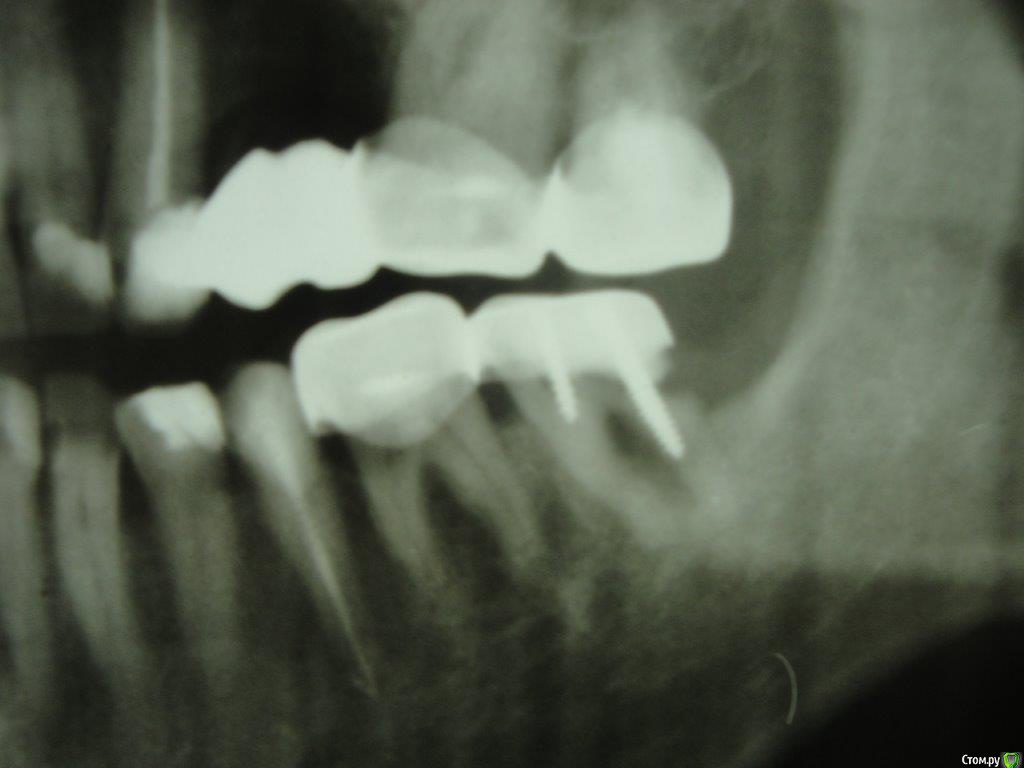

Коша Опубликовано 26 апреля, 2016 Поделиться Опубликовано 26 апреля, 2016 Здравствуйте!Подскажите пожалуйста!можно ли восстановить 7снизу слева зуб. пару врачей мне сказали, что нужно удалять, но вера в современную стоматологию, еще теплит надежду, что возможно еще можно над ним поработать, и пока оставить его!Зуб не болит, я им жую, но стала образовываться щель между телом зуба и краем коронки.Есть несколько снимков (отрывки с панорамных снимков)- прилагаю их. Ссылка на комментарий